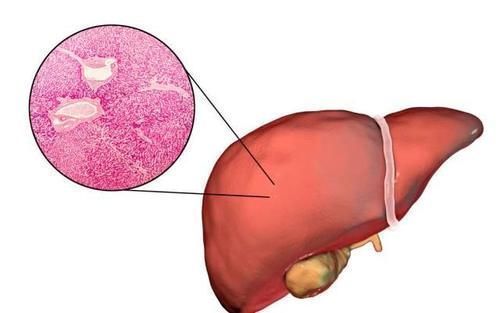

4、单纯性肝囊肿

文章插图

单纯性肝囊肿其实是一种良性病变,只有在囊肿大于3厘米或者出现腹胀的情况时才需要进行治疗,如果囊肿很小并不需要担心。